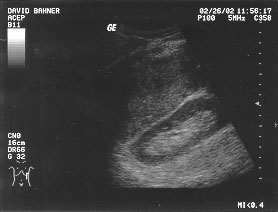

Cardiac - long parasternal (unlabeled)